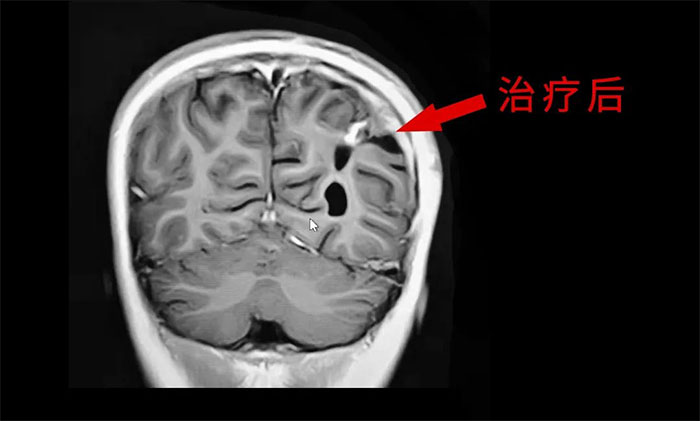

目前,腦膠質(zhì)瘤的治療方面,倡導(dǎo)MDT多學(xué)科診治,神經(jīng)外科、影像科、放射治療科、腫瘤科、病理科和康復(fù)科等多學(xué)科合作,遵循循證醫(yī)學(xué)原則,優(yōu)化和規(guī)范治療方案,采取個(gè)體化綜合治療,以期達(dá)到最大治療效益,盡可能延長(zhǎng)患者的無(wú)進(jìn)展生存期(PFS) 和總生存期(OS),提高生存質(zhì)量。

外科手術(shù)往往是膠質(zhì)瘤治療的第一步。手術(shù)原則是在最大范圍安全切除(maximal safe resection)腫瘤的同時(shí),保護(hù)神經(jīng)功能區(qū)。以解除占位征象和緩解顱內(nèi)高壓癥狀;解除或緩解因腦膠質(zhì)瘤引發(fā)的相關(guān)癥狀;獲得病理組織和分子病理,明確診斷;降低腫瘤負(fù)荷,為后續(xù)綜合治療提供條件。

放、化療等亦是不可或缺的重要治療手段,高級(jí)別膠質(zhì)瘤術(shù)后選擇標(biāo)準(zhǔn)同步放、化療可以取得顯著的生存獲益。

于耀宇主任特別指出,隨著腦血管介入技術(shù)快速發(fā)展,腦膠質(zhì)瘤術(shù)后超選介入化療聯(lián)合同步放療的效用正逐漸為大家所認(rèn)識(shí)。超選介入化療,是利用微導(dǎo)管技術(shù)直接將藥物通過(guò)供血?jiǎng)用},灌注到顱內(nèi)腫瘤組織區(qū)域,避免了傳統(tǒng)口服或靜脈注射藥物,要經(jīng)過(guò)全身代謝后才能到達(dá)腫瘤區(qū)域?蓽p輕全身毒性反應(yīng),延長(zhǎng)化療藥在腫瘤內(nèi)的滯留時(shí)間,更好地殺傷腫瘤細(xì)胞。

最后,于耀宇主任表示,膠質(zhì)瘤固然兇險(xiǎn),但我們應(yīng)當(dāng)正確認(rèn)識(shí)疾病,不盲目悲觀,更不應(yīng)輕易放棄治療。隨著醫(yī)療技術(shù)水平和治療手段的不斷提高,膠質(zhì)瘤患者在接受規(guī)范的治療后,延長(zhǎng)生存期已成為可能,大可不必“談瘤色變”。